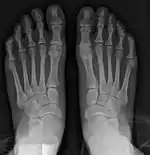

Fig. 8a. Painful hallux valgus and metatarsus primus varus deformity recurrence of left foot after osteotomy surgery

Other options

1. For severe bunion deformity correction (Fig. 7)

1. For recurrence correction after osteotomy procedure (Fig. 8)

Late deformity recurrence can happen after osteotomy (bone-breaking) procedures because osteotomy surgeries do not specifically stabilize first metatarsal bone.